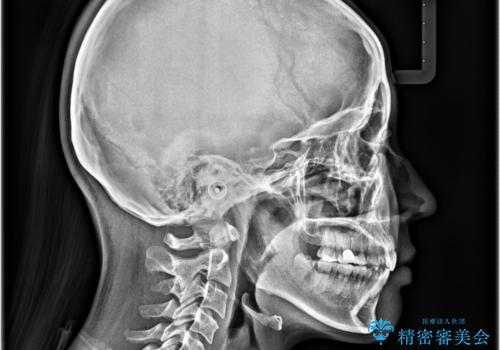

- 前歯が突出して、眠るときに口が開いてしまうことを気にして来院された患者様です。

横から見た際の口元の飛び出した印象も改善したいとのことで、上下左右の第一小臼歯4本を抜歯し、ワイヤー装置にて抜歯矯正を行うこととしました。

舌の突出癖改善のためのトレーニングをしっかりと実践してくださり、2年強の治療期間でしっかりと仕上げることができました。